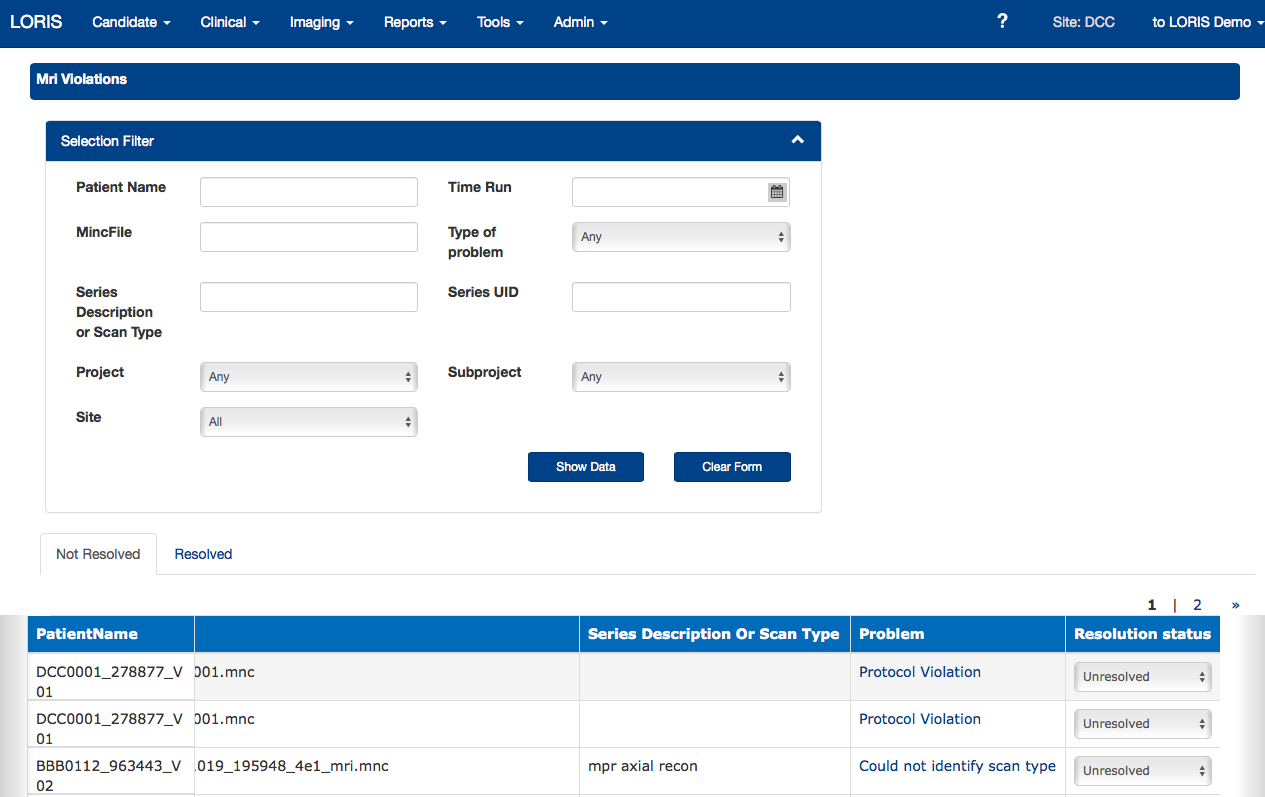

- Quality Control - Protocol violations, artefact detector, inter-rater reliability

Protocol Violations

Interactive Protocol Violations - New